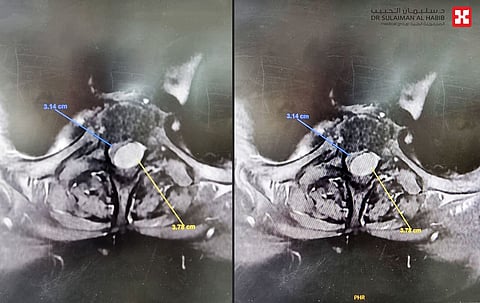

وعقب وصولها خضعت لحزمة من الفحوصات الدقيقة، وأظهرت صور الأشعة الطبية للعنق، وجود تضيق متوسط الحدة للقناة الشوكية العنقية من الفقرة الثالثة إلى الفقرة السابعة، بسبب تآكل الغضاريف وارتخاء الأربطة المحيطة بالنخاع، كما لوحظ وجود ورم غشائي سحائي، خلف الفقرتين الثانية والثالثة الصدرية.

وأوضح د. النبهان أن كلا الإصابتين تثيران الأعراض التي تشكو منها المراجعة، لذلك تم إعادة فحصها بالرنين المغناطيسي للتأكد من حجم الورم ومدى الضغط الذي يشكله على النخاع الشوكي، وتأكد من خلال النتيجة أن الورم هو المسبب الأساسي لمتاعب السيدة.